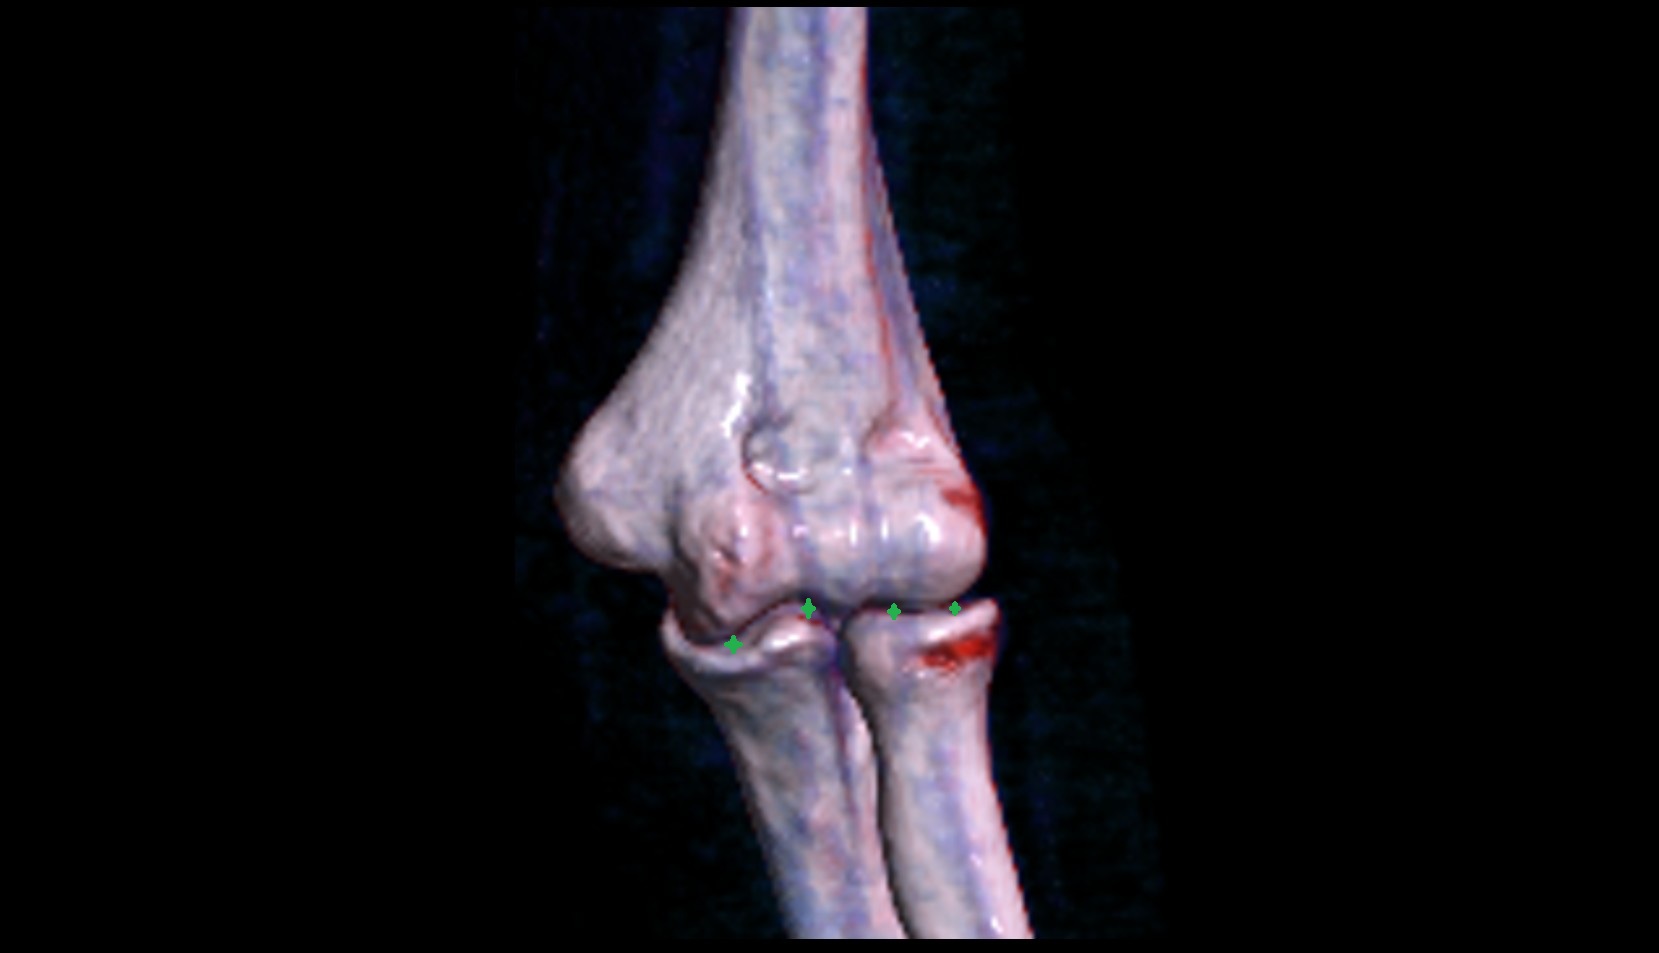

- Elbow joint

- Capitulum of humerus

- Trochlea of humerus

- Olecranon

- Coronoid process of ulna

- Head of radius